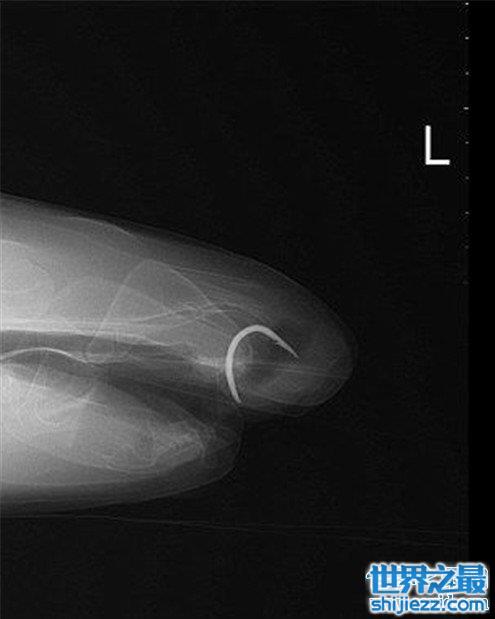

但是他的身材并不像是不喜欢实物那种,所以研究的人就把他带回来进一步做观察才发现,他的嘴里有一个鱼钩卡住了,这应该是他不想进食的主要原因,而研究人员看着鱼钩的情况,也发现这个鱼钩应该卡在这里很久了,都生锈了,于是研究人员赶快把他的鱼钩取出来。

并做了后面的修复手术,才得以让弗洛伦斯重新开始进食,但没想到的是,他再也不吃肉来了,估计是因为那个鱼钩给他造成了心理阴影,他上次应该也是因为贪嘴,吃了里面有鱼钩的肉类,让鱼钩卡在了自己嘴里,这让他以后再也不敢吃肉了,他怕再度被卡住,而研究人员现在也在尽快的恢复他原本吃肉的属性,如果他恢复不来,他和他的家族人员恐怕就难以相处了。